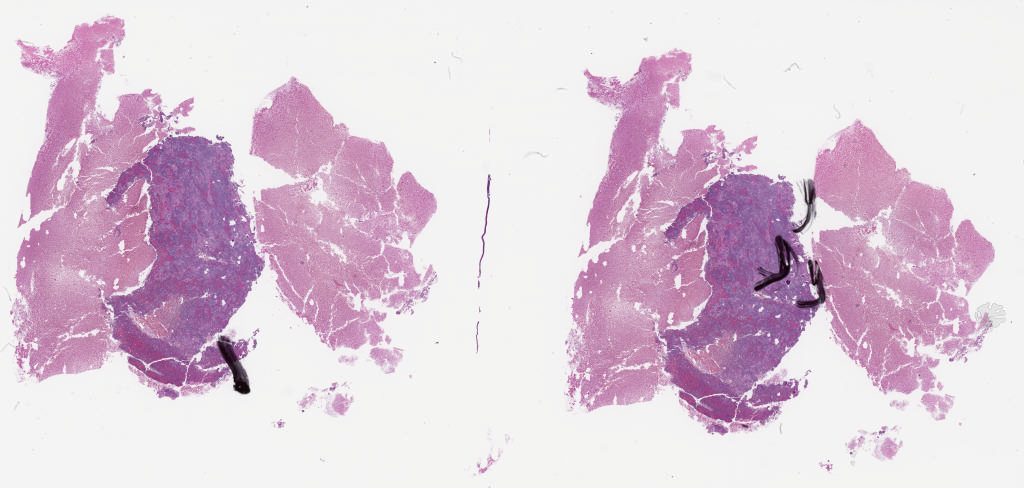

Case6 pap.svs

93624

x

89987

@

40X